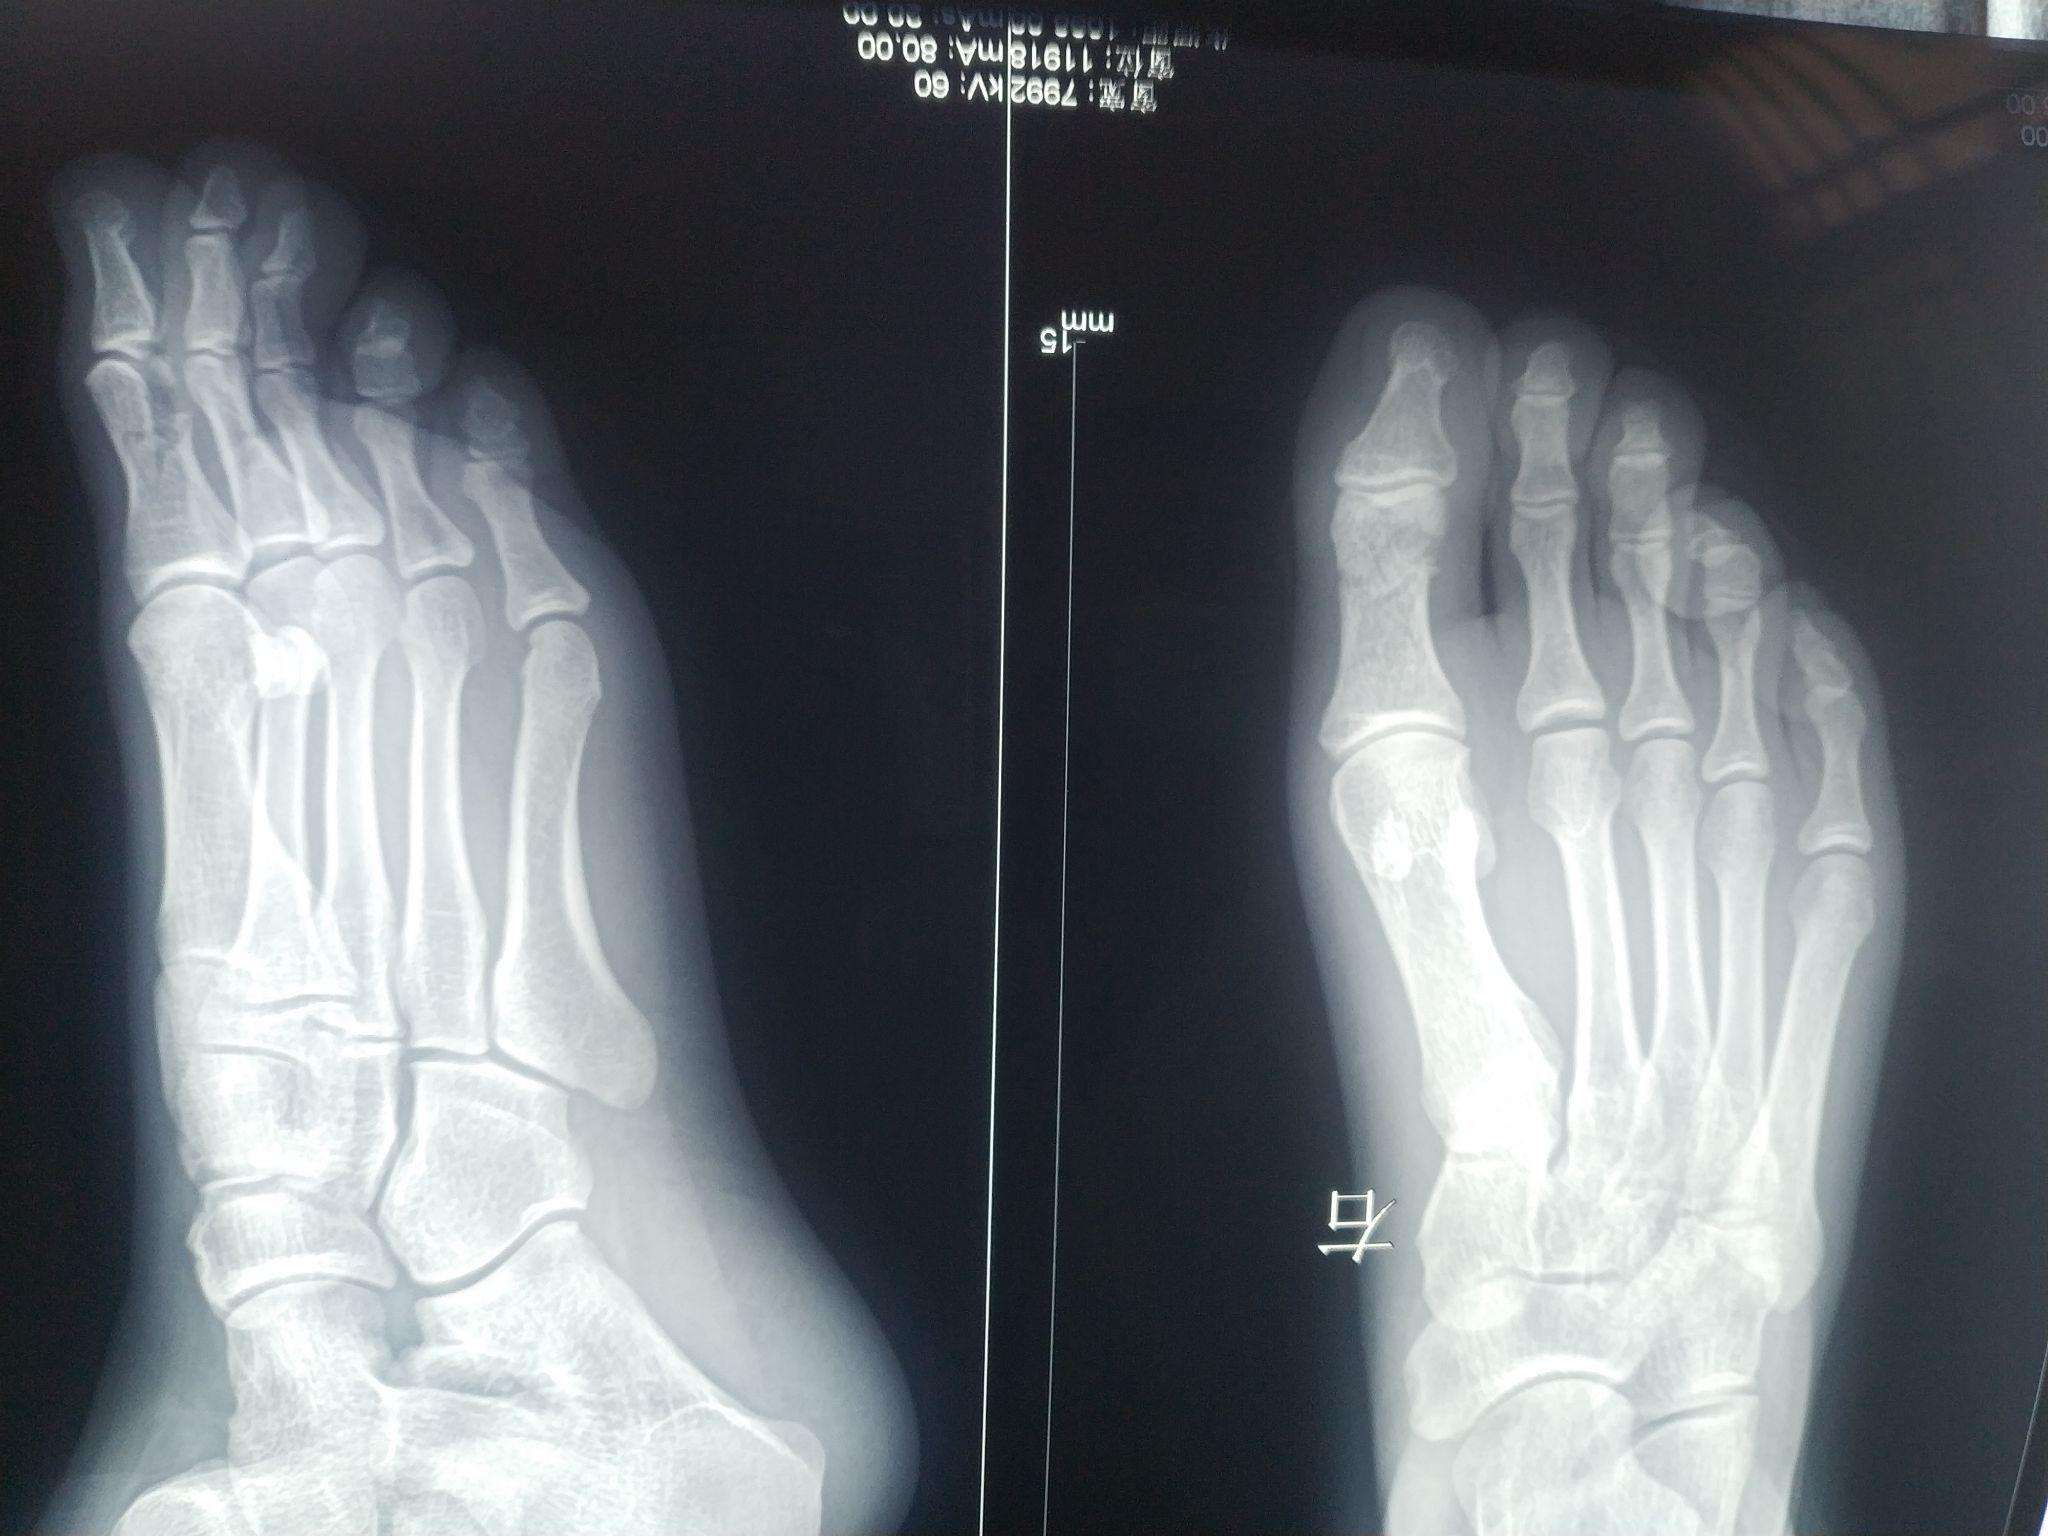

足拇指近节远端粉碎性骨折,微创手术解决大问题!

图片尺寸2183x1382